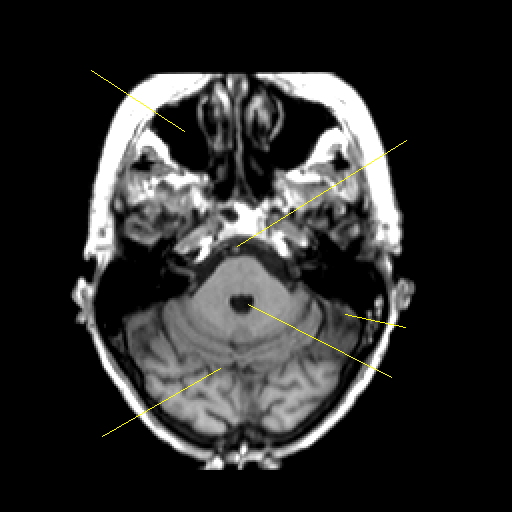

T1-weighted structural MR: Slice 14

Slice 14

Unlabeled

Pointers

Labeled